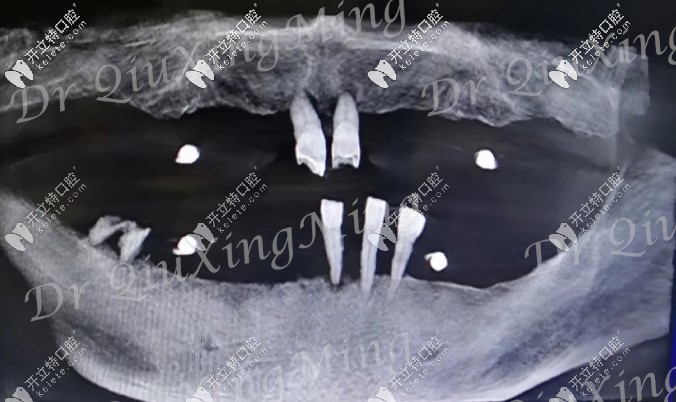

首先看下他的牙齒情況:嘴里還剩下5顆牙,還有2顆殘根,邱醫(yī)生建議全部拔掉,因?yàn)槟?顆牙也已經(jīng)松動(dòng)了,沒有保留的必要。

大爺口腔CT照

檢查顯示他的牙槽骨有部分吸收,一般的種植手術(shù)是需要植骨的,但邱醫(yī)生給他用的是all-on-4種植技術(shù),不用植骨,還可以選擇即拔即種的修復(fù)方式。